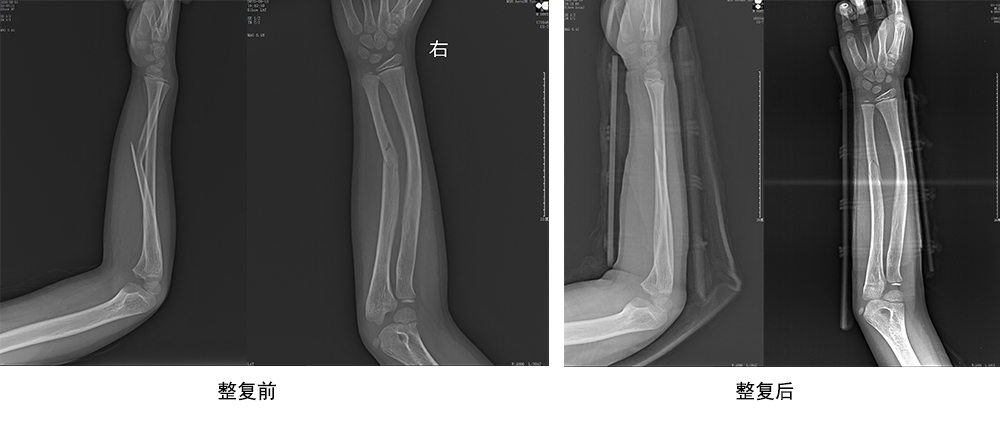

傳統(tǒng)手法整復(fù)病例影像

CR99142